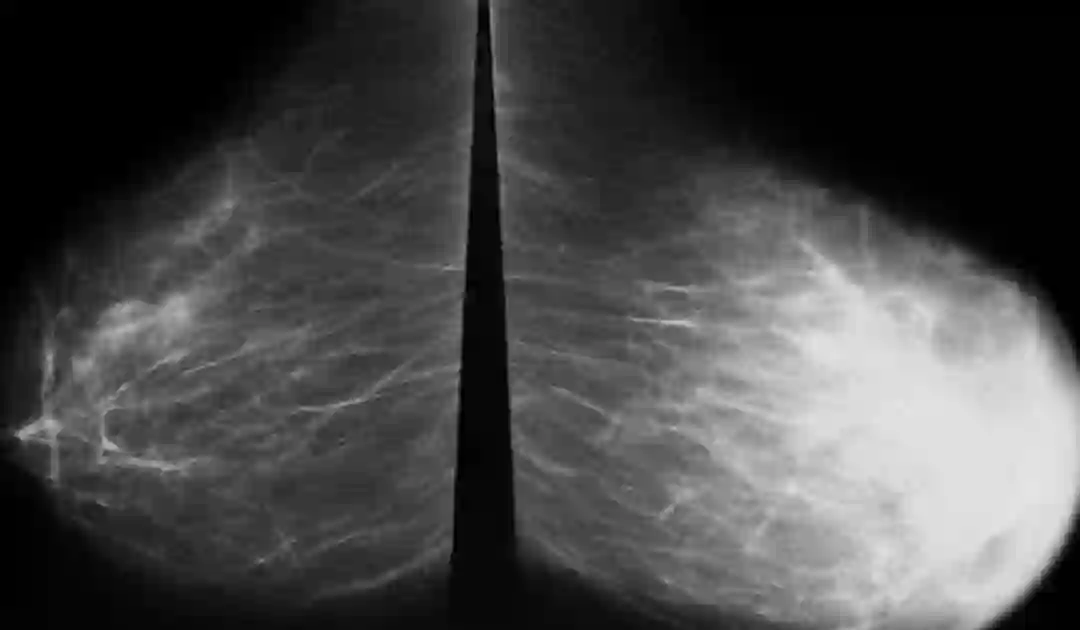

乳腺X线AI诊断

乳腺癌是全世界最常见的女性肿瘤并且是导致女性因肿瘤死亡的主要癌种。在我国,新诊断的乳腺癌病例占全球乳腺癌新发病例的12.2%,死亡率为9.6%,乳腺癌已经成为我国女性癌症死亡的主要原因之一,研究证实乳腺癌筛查与降低乳腺癌发病率及死亡率明显相关。

现阶段,国内针对乳腺影像的智能辅助诊断主要集中在乳腺钼靶领域。尽管超声作为指南推荐首选早筛方式,但由于超声检查影像结果受设备、操作人员、操作手法等差异较大的影响,且为动态图像,无法形成标准化数据集,故而训练难度极大,AI辅助诊断效果往往不尽如人意。相较之下,乳腺数字X线检查具有良好的对比度及分辨力,能够分辨组织间细微结构密度的差别,且操作简单,价格相对低廉,易于接受,诊断准确率较高,是国际上公认的乳腺癌早期机会性筛查及早期发现的有效措施。

目前已有数家厂商进军乳腺X线影像智能诊断领域并发布相关产品,大多数产品都具备了基础的肿块、钙化检出能力。少数领先厂商的系统不仅能检出肿块、钙化、结构扭曲、不对称,还能进行腺体分型、病灶检出以及全征象描述、BI-RADS分类、生成结构化报告等。医生在临床诊断过程中使用这些产品进行辅助判断,产品性能已达到临床可用程度,临床性能已接近资深的专业乳腺X线钼靶阅片医师。

国内外乳腺X线影像智能辅助诊断产品主要功能集中在钙化和肿块的检出以及病灶的分析方面。其中深睿医疗(DEEPWISE)、依图医疗(YITU)和腾讯觅影的产品市场试用规模较大,产品针对临床诊断辅助支持功能较完善。推想科技(infervision)、医准智能(MEDICAL AI)也相继在市场上发布了辅助产品。

国外在乳腺X线影像智能辅助诊断产品研发中较为突出的公司主要包括谷歌(google,DeepMind,美国)、英特尔(Intel,美国)、豪洛捷(Hologic,美国)、Medipattern公司(加拿大),其中Medipattern公司(加拿大)乳腺超声CAD设备B-CAD在2005年获得了FDA批准进入美国销售。英特尔(Intel,美国)在国内与汇医慧影公司合作,共同开发“人工智能乳腺全周期健康管理系统”助力乳腺癌早期筛查以及诊治。其中东软的乳腺X线计算机辅助检测(CAD)产品已经完成了国内国家食品药品监督管理总局(CFDA)的认证并有限投入市场进行使用。